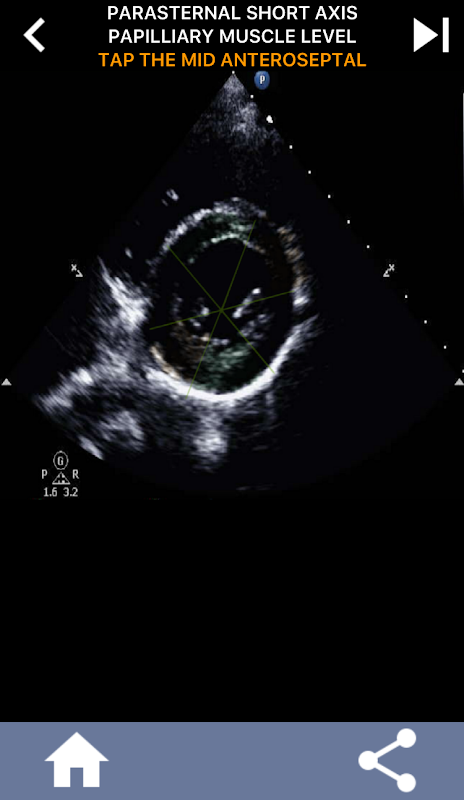

Phương pháp trực quan dựa trên câu hỏi để tìm hiểu các phân đoạn tim AHA: Siêu âm tim

Việc hiểu các phân đoạn tim của AHA (Hiệp hội Tim mạch Hoa Kỳ) là vô cùng quan trọng đối với kỹ thuật viên siêu âm tim để giao tiếp hiệu quả với bác sĩ tim mạch viết báo cáo. Bằng cách biết các vùng giải phẫu cụ thể và các phân đoạn tương ứng của chúng, kỹ thuật viên siêu âm có thể mô tả và truyền đạt chính xác bất kỳ sự bất thường hoặc phát hiện nào, đảm bảo giao tiếp rõ ràng và ngắn gọn giữa cả hai chuyên gia.

Sự hiểu biết này trở nên đặc biệt quan trọng khi bác sĩ tim mạch tìm cách xác định vị trí chính xác của vấn đề hoặc khi bác sĩ trực xác định vấn đề trong một khu vực cụ thể, khiến kỹ thuật viên siêu âm hiển thị chính xác phân đoạn tương ứng, chẳng hạn như thành giữa phía dưới. Do đó, nắm bắt toàn diện các phân đoạn tim AHA là bộ kỹ năng cần thiết.

Ứng dụng này sẽ kiểm tra kiến thức của bạn bằng cách sử dụng hình ảnh tiếng vang thực tế, mà tôi thường thấy là phương pháp giảng dạy tốt nhất.